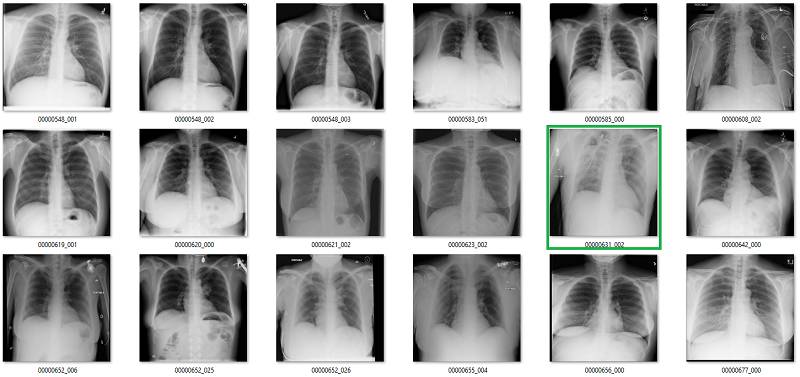

气胸(Pneumothorax)

气胸是指在肺部周围的胸膜腔空间有气体。这可能导致肺部瘫痪,因此它是非常严重的病变。但实际上,气胸在 X 光影像上非常微小,经常会被人忽略掉。

初次看来,标签似乎非常有效。在这 18 个样本中,只有用橙色标出的那张影像有点问题,这也可能是因为我没在诊断环境下查看肺部影像的原因。

但是绿框也有点问题,因为这些病人已经使用胸腔引流治疗过气胸。因此,现在有以下两个问题:

这并不是医学上重要的问题,我们希望避免气胸未被诊断出的错误,而这些图像标签确实没有犯这种错误。

如果很多影像都通过胸腔引流治疗,AI 系统将会学习识别胸腔引流而不是气胸。模型训练时的大多数图像样本批量完全可能包含有胸腔引流的气胸。